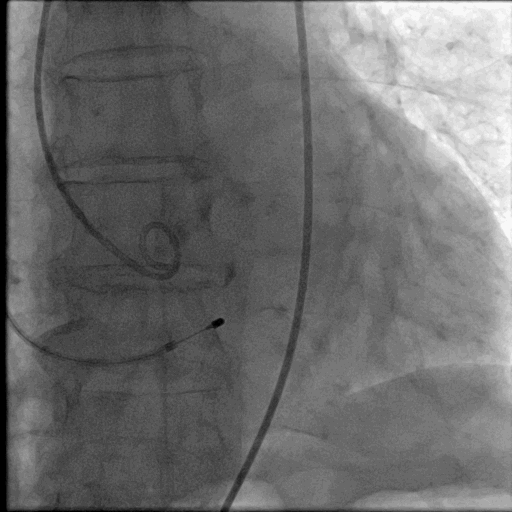

全麻气管插管,通过右颈内静脉留置临时起搏器于右室,以右侧股动脉作为主入路,经皮穿刺,预置2把Proglide缝合器。主动脉根部造影可见主动脉瓣钙化影,主动脉瓣中-重度返流。

TAVR术前主动脉根部造影

主动脉瓣跨瓣及球囊预扩张

送入猪尾导管至左心室,测量左室压力150/12mmHg,升主动脉压力110/35mmHg,跨瓣压差40mmHg。交换头端预塑形Cook Lunderquist超硬导丝至左心室,撤出猪尾导管。(如下图)

心脏临时起搏器快心室率起搏下启用23mmCRISTAL球囊行主动脉瓣球囊预扩张,再次行主动脉根部造影,提示球囊无腰征,并有部分造影剂渗漏。(如下图)